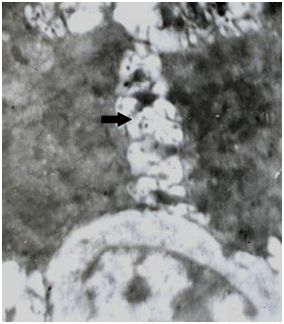

Epithelium: Marked intercellular gapping with interrupted basal lamina with focal deposition of basement membrane like material in wide areas of the sub-epithelial layer (Figure 2 & 3).

Figure 2 Electron micrograph showing parts of two adjacent basal epithelial cells with slightly widened intercellular spaces (arrow), a normal nucleus (N) and multilayered disrupted basal lamina (BL). (EMx6000).

Figure 3 Electron micrograph showing parts of adjacent epithelial cells with marked widening of intercellular spaces (arrow) (EM x4600).